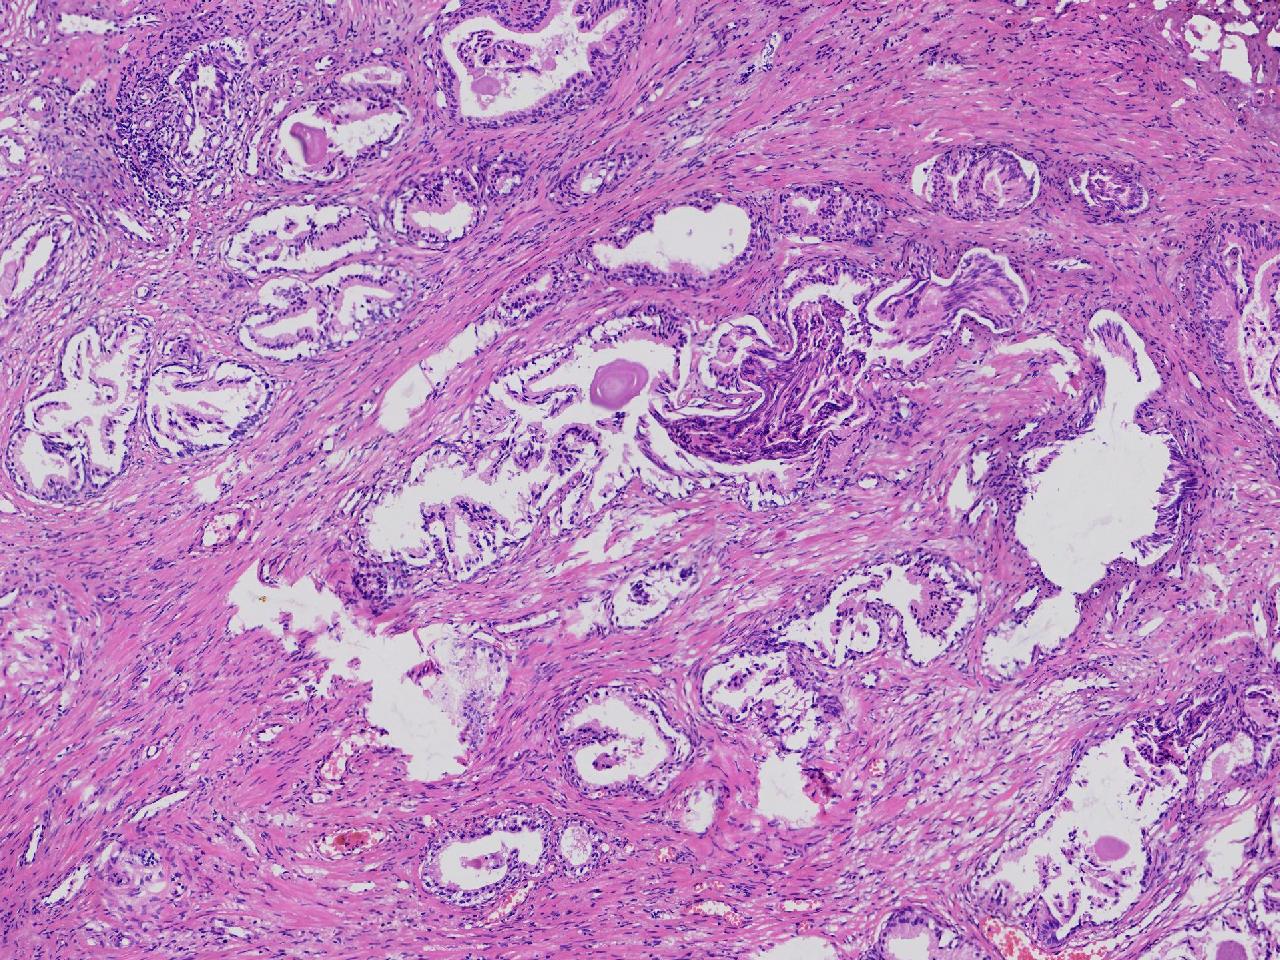

这些腺体有问题吗?

男,77岁,排尿困难2年,尿潴留3天。

标本名称

电切前列腺组织

图4